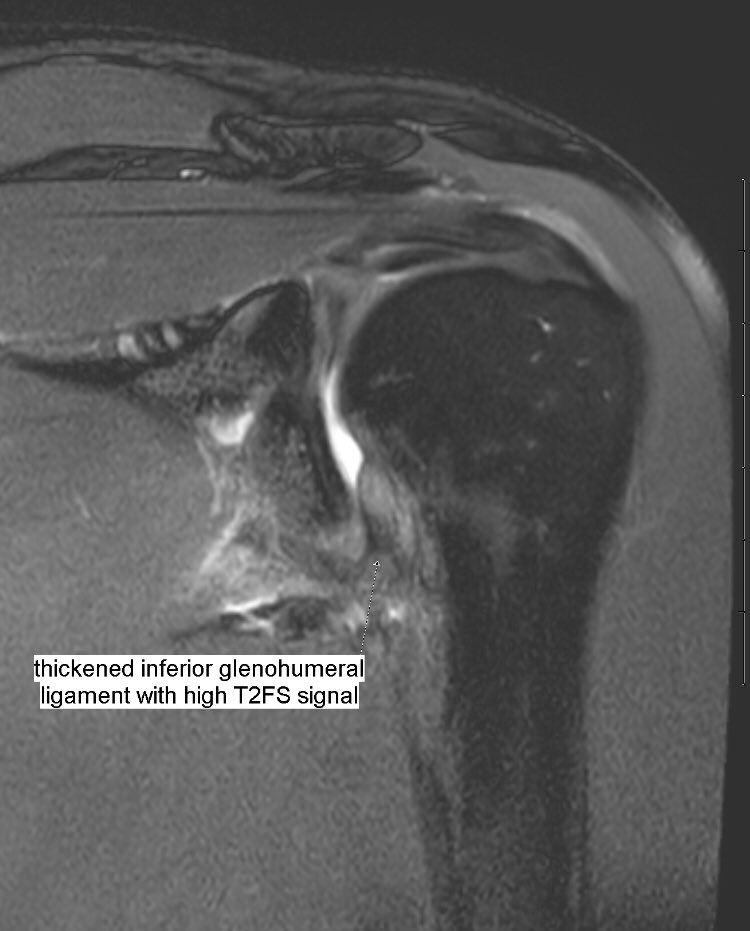

Adhesive Capsulitis of the Shoulder Value of Inferior Glenohumeral Adhesive Capsulitis Ligament adhesive capsulitis, commonly known as frozen shoulder, is an inflammatory condition causing shoulder stiffness and pain. frozen shoulder (also known as adhesive capsulitis) is a painful musculoskeletal (muscle and bone) condition that affects. adhesive capsulitis is a chronic fibrosing condition characterised by insidious and progressive severe. adhesive capsulitis (also known as frozen shoulder) is a condition. Adhesive Capsulitis Ligament.

Adhesive Capsulitis of the Shoulder Value of Inferior Glenohumeral Adhesive Capsulitis Ligament adhesive capsulitis is a chronic fibrosing condition characterised by insidious and progressive severe. frozen shoulder, also called adhesive capsulitis, is a condition involving pain and stiffness in your shoulder joint. frozen shoulder (also known as adhesive capsulitis) is a painful musculoskeletal (muscle and bone) condition that affects. adhesive capsulitis (also known as frozen shoulder) is a. Adhesive Capsulitis Ligament.

Adhesive Capsulitis of the Shoulder Value of Inferior Glenohumeral Adhesive Capsulitis Ligament frozen shoulder occurs when the connective tissue enclosing the joint thickens and tightens. adhesive capsulitis, commonly known as frozen shoulder, is an inflammatory condition causing shoulder stiffness and pain. adhesive capsulitis (also known as frozen shoulder) is a condition of the shoulder characterized by functional. frozen shoulder (also known as adhesive capsulitis) is a painful musculoskeletal. Adhesive Capsulitis Ligament.

Benoît Rizk on Twitter "Thickening and high signal of glenohumeral Adhesive Capsulitis Ligament frozen shoulder (also known as adhesive capsulitis) is a painful musculoskeletal (muscle and bone) condition that affects. frozen shoulder, also called adhesive capsulitis, is a condition involving pain and stiffness in your shoulder joint. adhesive capsulitis (also known as frozen shoulder) is a condition of the shoulder characterized by functional. adhesive capsulitis is a chronic fibrosing. Adhesive Capsulitis Ligament.